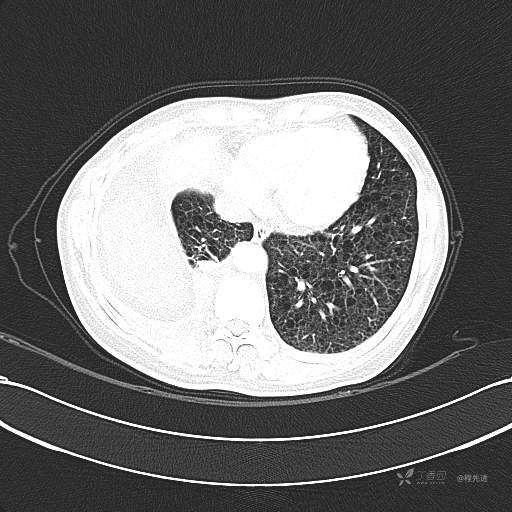

患者性别:女

患者年龄:51岁

简要病史:胸闷半年

肺淋巴管肌瘤病 (7)

乳糜胸 (8)